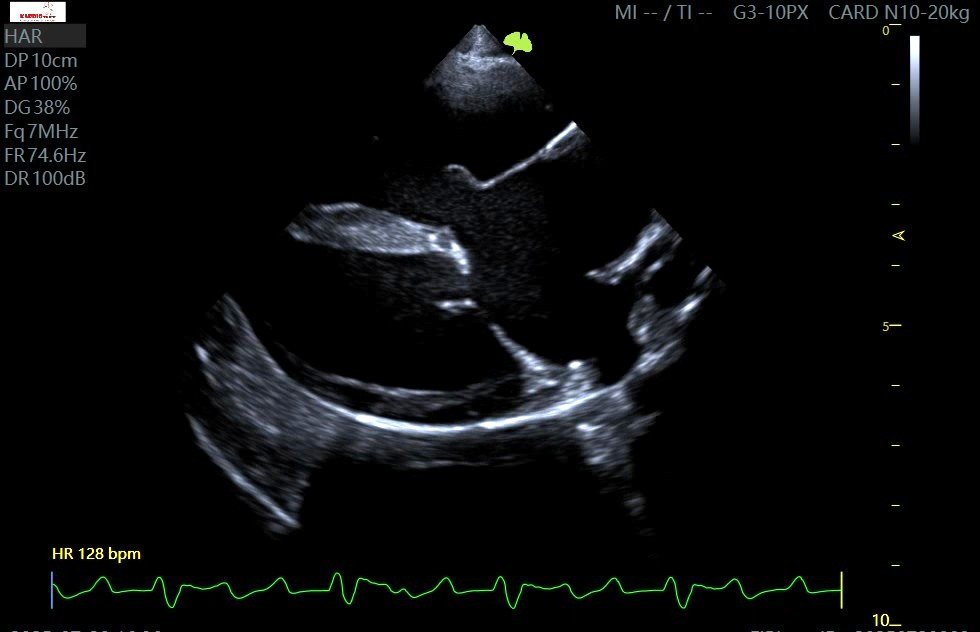

Najważniejsze nieprawidłowości stwierdzone w badaniu echokardiograficznym:

• Znacznej wielkości ubytek w przegrodzie międzyprzedsionkowej z przepływem:

• Dysplazja zastawki trójdzielnej:

• ograniczona ruchomość płatków

• szczątkowy płatek przyprzegrodowy

• nadmiernie długi płatek wolnej ściany

• istotna niedomykalność zastawki

• Wtórne znaczne powiększenie prawego przedsionka i prawej komory

• Spłaszczenie przegrody międzykomorowej z paradoksalnym jej ruchem oraz widoczny pseudoaneuryzm przegrody międzykomorowej w okolicy pod zastawką aortalną z możliwym przeciekiem lewo-prawym

• Dysplazja zastawki mitralnej (o mniejszym nasileniu), z niedomykalnością

• Zachowana czynność skurczowa lewej komory przy jednoczesnym upośledzeniu jej funkcji rozkurczowej

Na podstawie całości obrazu rozpoznano: Częściowy kanał przedsionkowo-komorowy (PAVC).

PAVC- obraz B-mode